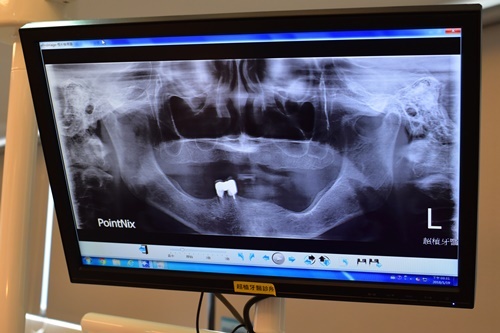

護士帶阿嬤去斷層掃描了,檢查口腔狀況。口腔報告馬上出來,諮詢師簡單為我們解說阿嬤口腔狀況。原來如果想做植牙,除了電腦斷層掃描、骨頭密度、咬合情形外,吳立琳醫師也會要求患者進行健康檢查。諮詢師進一步說明,像是有服用抗骨質疏鬆症藥物、自體免疫疾病藥物、抗凝血藥物或高血壓、糖尿病控制不佳的慢性病患,傷口癒合困難,吳醫師就不建議植牙了!